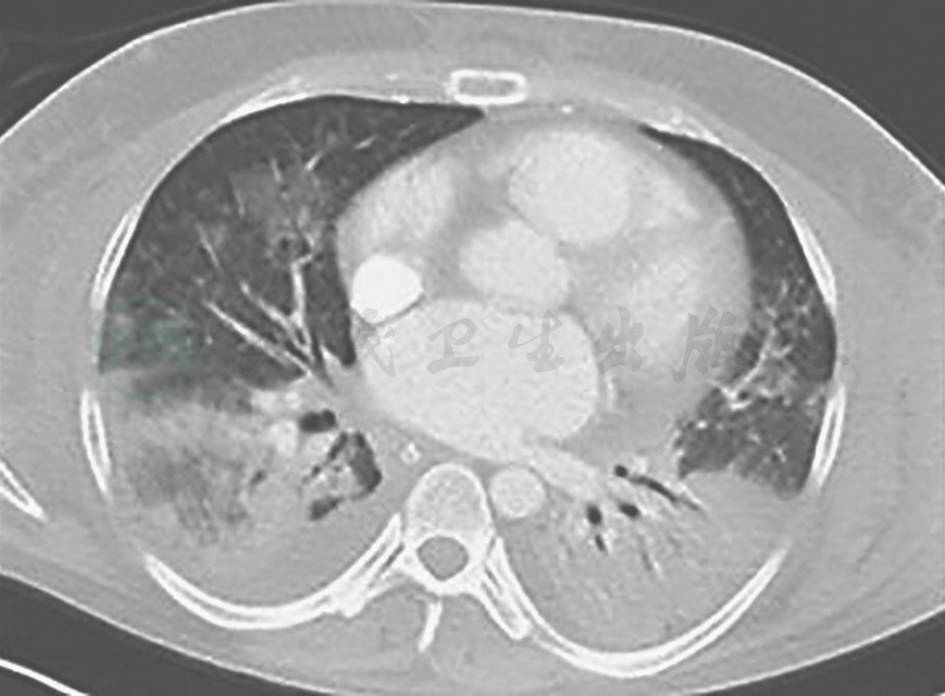

胸部CT:双肺多发高密度实变影,病灶以双肺中下为主(图11)。

图11 入院后复查CT表现

明确诊断后,考虑到患者双肺多发病变,无手术指征,采取停用前述抗感染药物,给予甲泼尼龙,患者未再发热,咳嗽、咳痰、胸痛症状缓解,但复查胸部CT仍显示病变进一步发展(图13)。

图13 激素治疗18天后复查胸部CT表现

胸部CT可见双肺病灶进一步增多,以结节和团块状实变为主